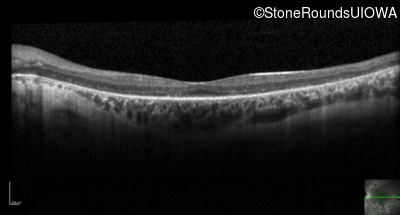

Optical Coherence Tomography - Right - 20/60 +1 sc

Exemplar / OCT Stack

OCT Stack